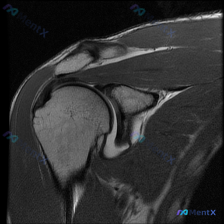

整理了一份肩部影像病例资料,核心情况如下: 1. 影像资料:肩部MRI T1加权冠状位序列 2. 核心疑问:临床怀疑盂唇病变,该序列影像下能观察到什么? 3. 初步影像所见:当前序列显示肱骨头、肩峰、冈上肌腱等结构大致完整,上方盂唇形态及信号未见明显异常,未见明确肩袖撕裂、骨性撞击征象。 想和大家讨...